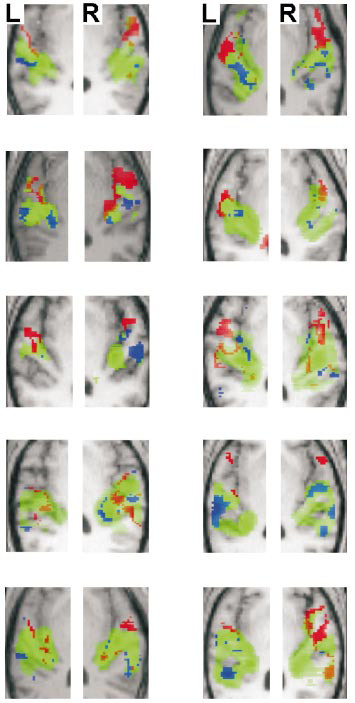

Fig. 4: Statistical parametric maps for individual subjects. Activated voxels (p < 0.001 uncorrected) are rendered on each individual’s structural MRI. The axial section is tilted to run along the superior temporal plane as in Figure 3 and the contrasts and colour key are the same as in Figures 3a and 3d. Bilateral areas including medial Heschl’s gyrus (HG) are activated in the contrast between broadband noise and silence (green). After exclusive masking of voxels activated both by pitch chroma change and by pitch height change, the two pitch dimensions show distinct activation patterns in most individuals: pitch chroma change (but not pitch height change) activates mainly areas anterior to HG on the planum polare (red); pitch height change (but not pitch chroma change) activates mainly planum temporale (blue).